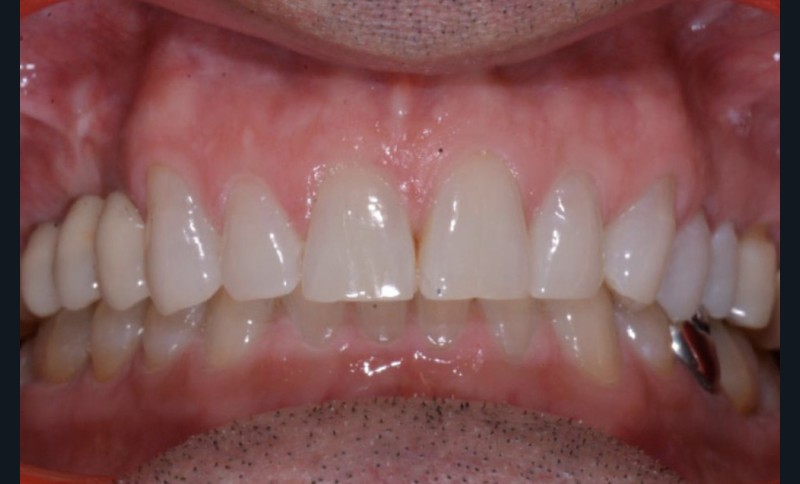

Conclusion

Les techniques orthodontiques de déplacement par gouttières orthodontiques thermoformées sont très efficaces pour gérer des situations simples. Ce patient en montre l’intérêt, en particulier lorsque la forme d’arcade dentaire doit être maintenue. Les systèmes « in-office » peuvent tout à fait permettre la gestion de ces situations.